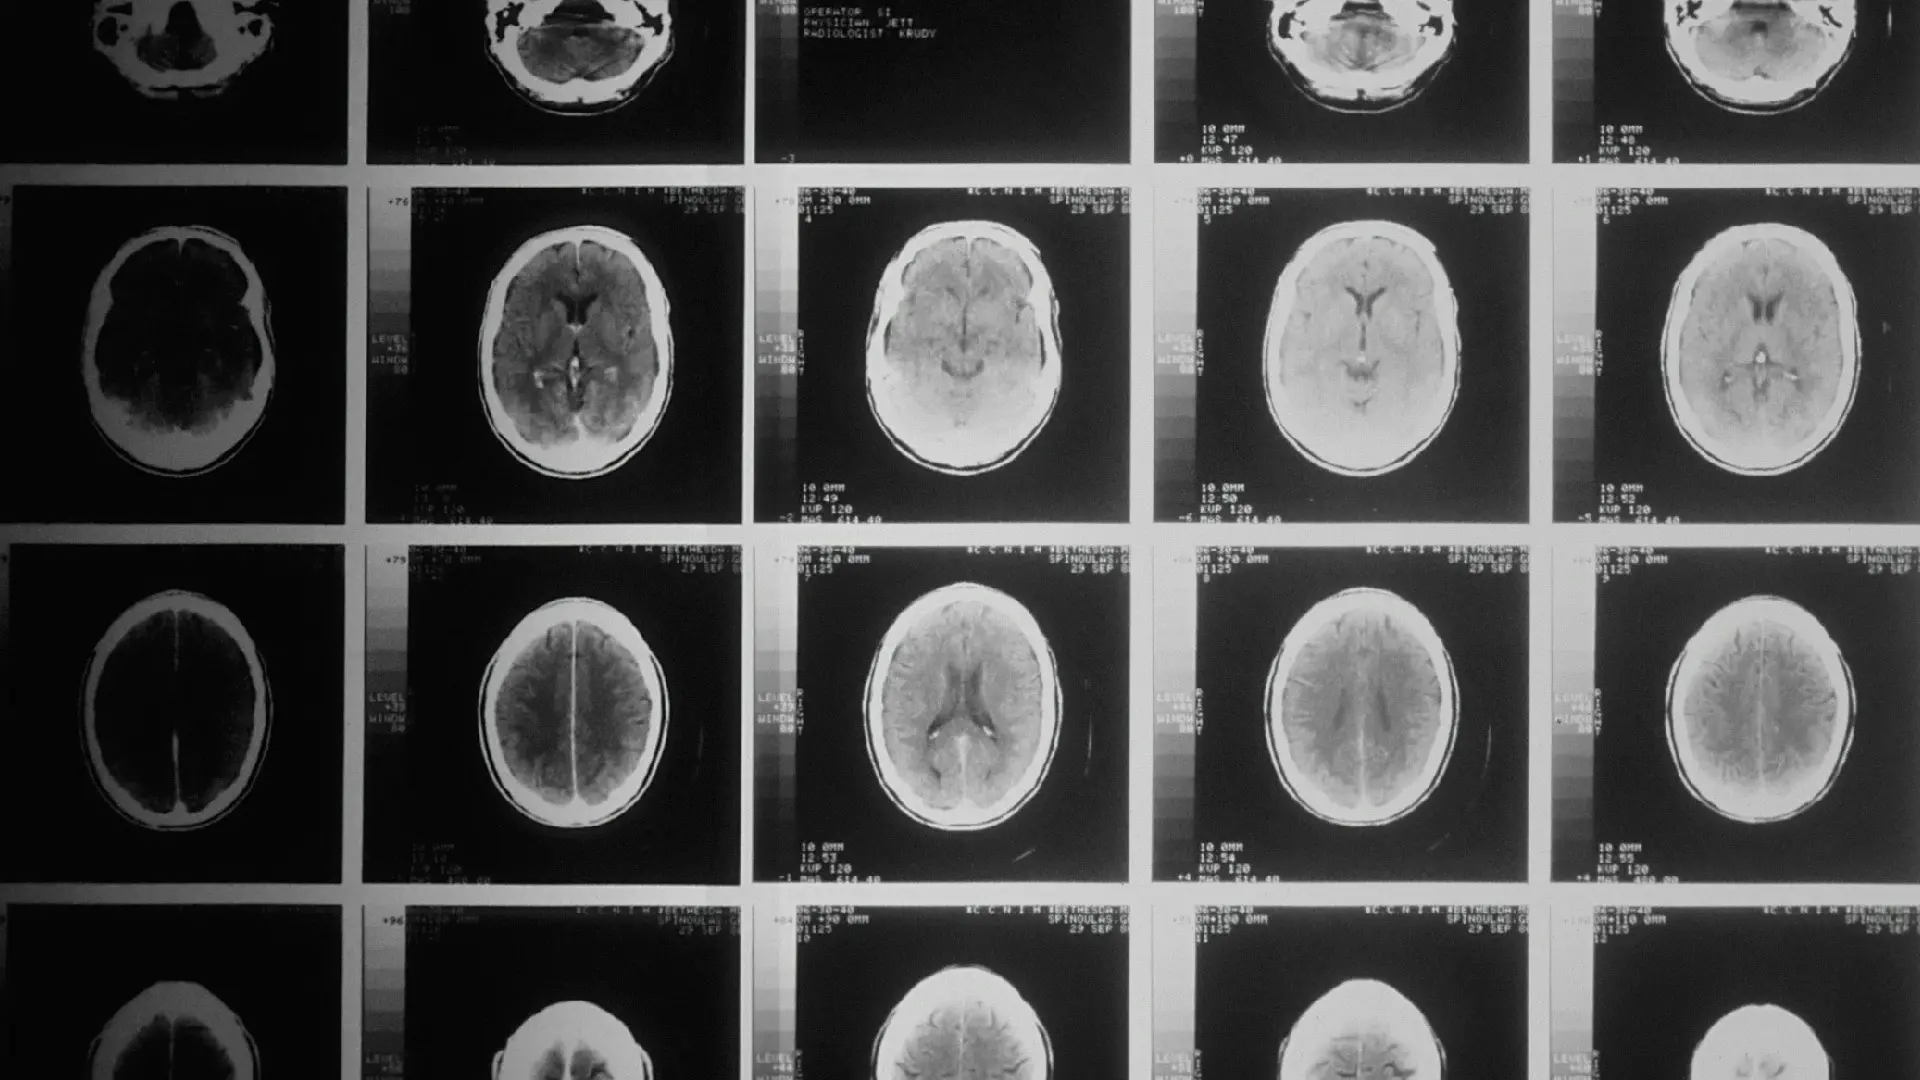

Innovative artificial intelligence (AI) advances in healthcare can improve the lives of humans throughout the world and speed up research in key areas. Through the thoughtful and sensitive use of AI, medical practitioners can make better decisions for their patients, healthcare management can be streamlined, and lives can be saved.